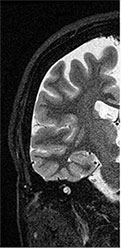

![]() MRI画像 |

脳梗塞、脳腫瘍、脳出血、その他の変性疾患を診断することができます。また、造影剤を用いること無く、血管を明瞭に描出し、動脈の瘤や狭窄を診断することができます。